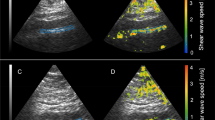

This was a cross-sectional study of 298 children and adolescents (48.0% male, body mass index: 27.0 ± 8.9 kg/m2), including 49 self-reported cases with SHS. Arterial elasticity and stiffness (distensibility, compliance, incremental elastic modulus [IEM]) were obtained via ultrasound imaging in the abdominal aorta, brachial, and carotid arteries. A one-way analysis of variance compared differences between groups, and multiple linear regression adjusted for covariates.

SHS was associated with lower abdominal aorta diameter distensibility (aDD) (13.4 ± 3.6% vs. 16.0 ± 5.2%, p = 0.009) and abdominal aorta cross-sectional distensibility (aCSD) (28.8 ± 8.3% vs. 35.1 ± 12.2%, p = 0.009), as well as higher abdominal aorta IEM (aIEM) (1241 ± 794 vs. 935 ± 388 mmHg, p = 0.001). After adjustment for covariates, aDD (p = 0.047), aCSD (p = 0.040), and aIEM (p = 0.017) remained significant; this significance persisted with the additional adjustment of percent body fat. Measures of brachial and carotid compliance and distensibility were not associated with SHS.

SHS was associated with abdominal aorta stiffness; the majority of vascular measures within the brachial and carotid artery remained unaffected following adjustment for covariates, including hypertension and adiposity. SHS may predispose individuals to increased abdominal aorta stiffness, an artery previously reported to exhibit increased susceptibility to atherosclerosis.